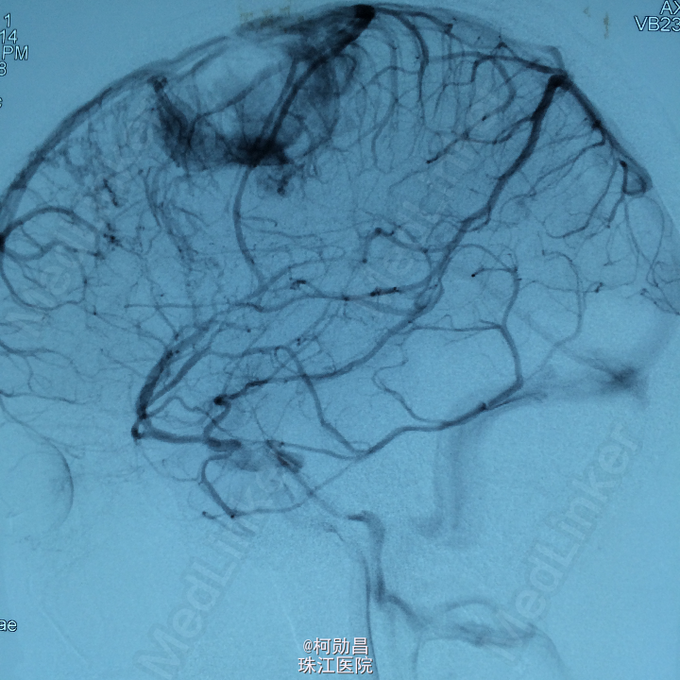

诊断:左侧顶叶占位 处理:行DSA检查,提示肿瘤染色,予PVA颗粒行血管内栓塞治疗。

术后再予开颅手术治疗,书中见供血动脉闭塞,出血量少。